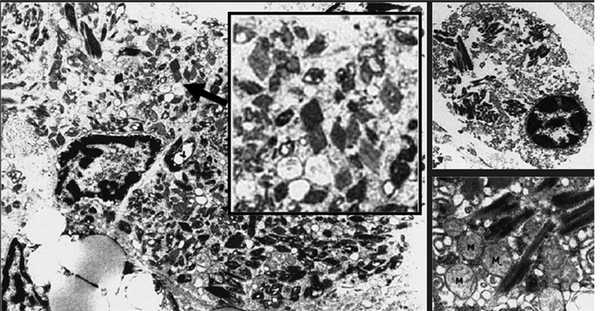

Возможны и другие формы ассоциированной с MGUS тубулопатии. Хорошо известно, что ЛЦ способны подвергаться реабсорбции и кристаллизации в цитоплазме канальцевого эпителия с развитием различных дисфункций канальцев — парциальных или по типу синдрома Фанкони. Кристаллизация Л.Ц. является фактором трансформации канальцевого эпителия в клетки макрофагального ряда с развитием гистиоцитоза (рис. 1). Однако следует отметить, что такая кристаллизация происходит во многих тканях и связана с тем, что лизосомальный аппарат резидуальных макрофагов оказывается неспособным полностью лизировать ЛЦ. У пациентов в этом случае нередко развивается генерализованный гистиоцитоз. Способность канальцевого эпителия почек трансдифференцироваться в клетки макрофагального ряда хорошо известна, это свойство является важным механизмом фиброза в почках у больных с протеинурией. Способность к трансдифференциации, по-видимому, связана с единством происхождения канальцевого эпителия и макрофагов из одного и того же эмбрионального листка — мезодермы.

Рис. 1. Гистиоцитоз с внутриклеточными кристаллами (A. Lebeau, E. Zeindl-Eberhart, 2002).